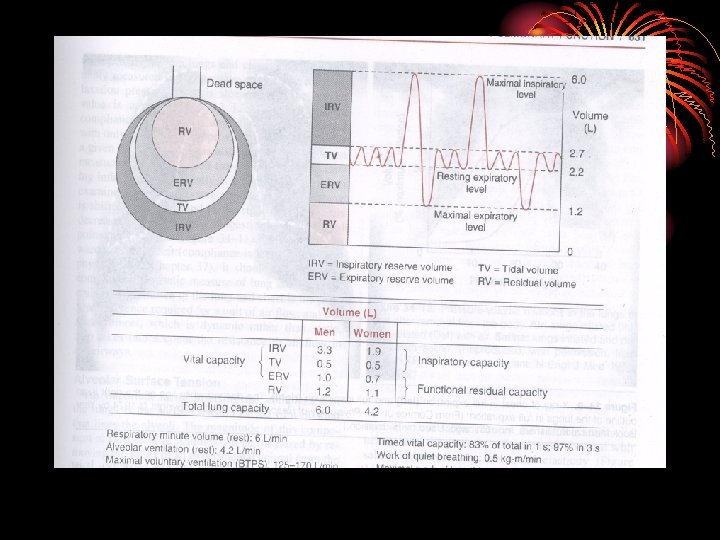

Lung volumes • Tidal volume: is the amount of air that moves into the lung with each normal inspiration. • Inspiratory reserve volume: amount of air inspired by a max. insp. after a normal insp. • Residual volume: amount of air left in the lungs after max. exp.

• Expiratory reserve volume: amount of air expired by a max. exp. After a normal exp. • Respiratory minute volume: (Pulmonary ventilation) amount of air inspired per min.

Capacities • Vital capacity: amount of air expired by a max exp. after a max. insp. • Inspiratory capacity: amount of air inspired by a max. insp. after a normal exp. • Expiratory capacity: max exp. after normal insp. • Total lung capacity: amount of air present in lungs after max. insp.